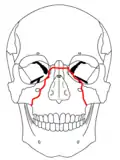

A principios del siglo XX, René Le Fort trazó ubicaciones típicas para las fracturas faciales, éstas ahora son conocidas como I, II y III fracturas de Le Fort (derecha).[5][2][6]

La fractura de Le Fort tipo II, también llamada fractura piramidal del maxilar,[7][10] cruza los huesos nasales y el reborde orbitario.[9]